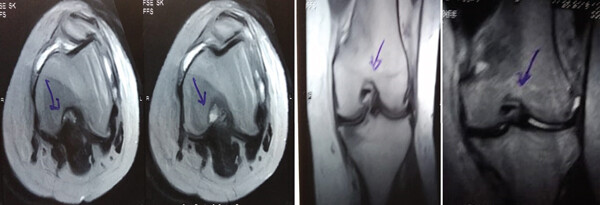

MRI:治療前后的MRI結果

治療前后的MRI結果

治療前 MRI 顯示內側和外側半月板后角 III 級撕裂。

治療后MRI檢查顯示內側和外側半月板后角撕裂有所改善?;颊甙Y狀改善,日常生活活動(dòng)能力增強。

結論:間充質(zhì)干細胞治療后,MRI檢查顯示內側和外側半月板后角撕裂有所改善 ,關(guān)節功能也有改善,未出現嚴重不良事件。可以達到干細胞治療半月板損傷短期療效的目標。